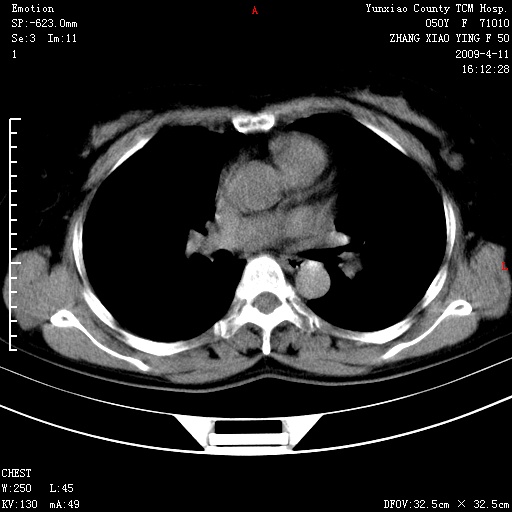

标题: CT19324:胸闷1周伴咳嗽 [打印本页]

标题: CT19324:胸闷1周伴咳嗽

病灶周围肺纹受压移位走行较柔和,余肺里实质均匀,纹理如常,肺间质无显著纤维化,支持考虑孤立性肺囊肿

考虑右肺中叶肺囊肿。